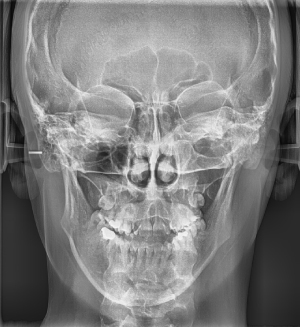

PA kefalogram

Postero-anteriorni snimak glave ili Caldwell-ova projekcija je takodje snimak koji se najčešće radi za potrebe postavljanja ortodontske dijagnoze i plana terapije kod pacijenata sa asimetrijama lica. Na ovom snimku ortodonti rade kefalometrijska merenja, a na osnovu njih i različite analize koje im pomažu u postavljanju dijagnoze i pravljenju plana terapije.